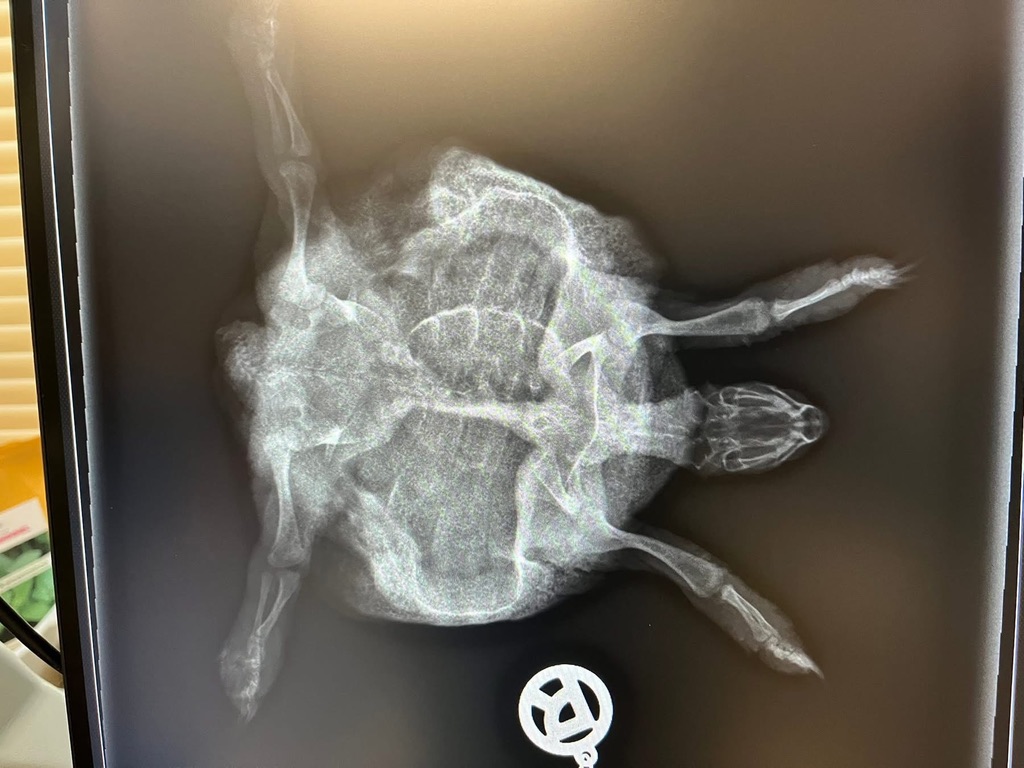

Weil sie dort durch die große Wärme ohne Starre wesentlich schneller wachsen als physiologisch vorgesehen, diese Tiere sind meist zu schwer für ihre Beine und ihr gesamtes Skelett, wodurch ihre Knochen und ihr Panzer ineinandersacken (Rachitis). Ihre zu schnell gewachsenen, großen Organe werden im Panzer eingequetscht und sie neigen von klein auf zu Höckerbildung und Organschäden. Mehr zum Thema Terrarienhaltung kann man hier nachlesen. Als stille Zeugen einer Terrarienhaltung sollen stellvertretend die nachfolgenden Bilder sprechen.